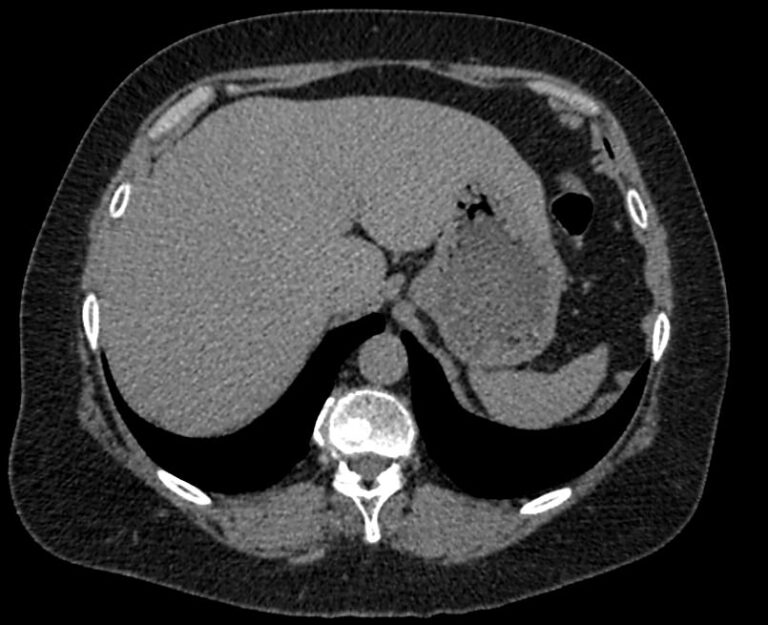

Мультиспиральная компьютерная томография (МСКТ) брюшной полости относится к современным лучевым методам исследования, с помощью которого можно оценить состояние органов брюшной полости (печени, желчного пузыря, поджелудочной железы, селезенки), прилегающих к ним кровеносных сосудов и лимфатических узлов.

С помощью мультиспиральной компьютерной томографии проводятся послойные рентгеновские снимки исследуемой области с толщиной среза от 0,5 мм. В нашей клинике исследование выполняется на компьютерном томографе экспертного класса TOSHIBA AQUILION CXL, который оснащен 128 детекторами, позволяющими получать за несколько секунд снимки брюшной полости с высокой точностью. Большое количество детекторов позволяет получить точные данные, при этом сократить время исследования и сделать минимальной лучевую нагрузку на пациента. Кроме того, инновационные технологии аппарата дают возможность сформировать объемную модель органа и окружающих структур, что также способствует проведению точной и достоверной диагностики.

При подозрении на опухоли, воспалительные процессы, гнойные очаги назначается КТ брюшной полости с внутривенным болюсным контрастированием. Для этого пациенту внутривенно вводится рентгеноконтрастное вещество на основе йода. Благодаря усиленному кровоснабжению препарат накапливается в структуре патологических образований и помогает врачу-рентгенологу выявить изменения в структуре внутренних органов.

Метод контрастирования помогает максимально точно выявить очаг патологии уже на начальной стадии, а также установить его локализацию, точные размеры, форму и особенности кровоснабжения.